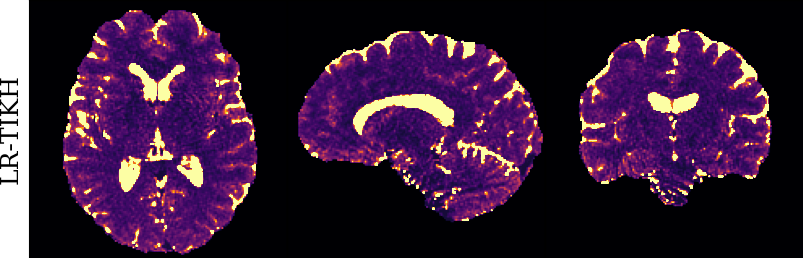

To monitor performance progress, we mapped TSMI to Q-Maps every five epochs. To mitigate the lengthy processing times associated with Dictionary Matching, we implemented a fully connected network to directly map TSMI to Q-Maps [5], significantly reducing processing time. However, for the final assessment, we employed DM on all techniques at the conclusion of the training process (epoch 500). We report in Table 1 the Mean Average Percentage Error (MAPE) of T1/T2 maps, and Peak Signal-to-Noise Ratio (PSNR) and Structural Similarity (SSIM) Index for T1/T2 and normalised PD. To accompany these metrics we also offer in Fig. 2 the reconstructed T1 and T2 maps for the different approaches.

The training and validation loss (Fig. 1) served as valuable guides for architecture and training design. To demonstrate this, we selected a subset of experiments in which we kept certain variables fixed and only modified the one under inspection. From Fig. 1 (a)-(d), MAPEs curves show there is a clear setting with the preferred performance. Specifically, from Fig. 1a, it is evident that using DRUNet yields a clear improvement over the original architecture. This could be attributed to the utilisation of residual units in addition to other architecture differences, such as the choice of upsampling operator (transpose convolution for DRUNet and trilinear for DIP). The choice of input (Fig. 1b) demonstrated a consistent pattern among the tested options, with low rank (conjugate gradient) initialiser marginally outperforming the others. Fig. 1cshows that by epoch 100, stochastic approaches exhibit lower reconstruction errors compared to non-stochastic methods. For example, adaptive LR with stochastic training yields a combined MAPE of 61.40% (17.09% T1 and 44.31% T2) vs. 213.69% (35.50% T1 and 178.19% T2) for the non-stochastic method. This fast convergence is due to adaptive LR and stochastic updates across coils. Despite similar execution times ( 34 min for stochastic with adaptive LR vs. 32 min for non-stochastic with fixed LR), the rapid error reduction makes StoDIP more attractive for training.. To assess the early stopping of DIP models, a key element, we present Fig. 1d. The original work by Ulyanov et al. [21] used 2k iterations, while Hamilton et al. [12] used 30k. In contrast, our settings show StoDIP achieving competitive performance in under 500 epochs (4k iterations) on the entire volume. However, StoDIP can overfit to k-space measurements, affecting reconstruction accuracy, and thus the iteration at which it stops could have a greater impact. We show that adding a spatial penalty term addresses overfitting and instabilities. This is supported by the maps in Fig.2, supplementary material Figures 1-3, and metrics in Table 1. StoDIP reconstructions lack aliasing artifacts, and the TV regularizer (StoDIP + TV) further improves Q-Map reconstruction by reducing checkerboard artifacts observed in StoDIP outputs alone.